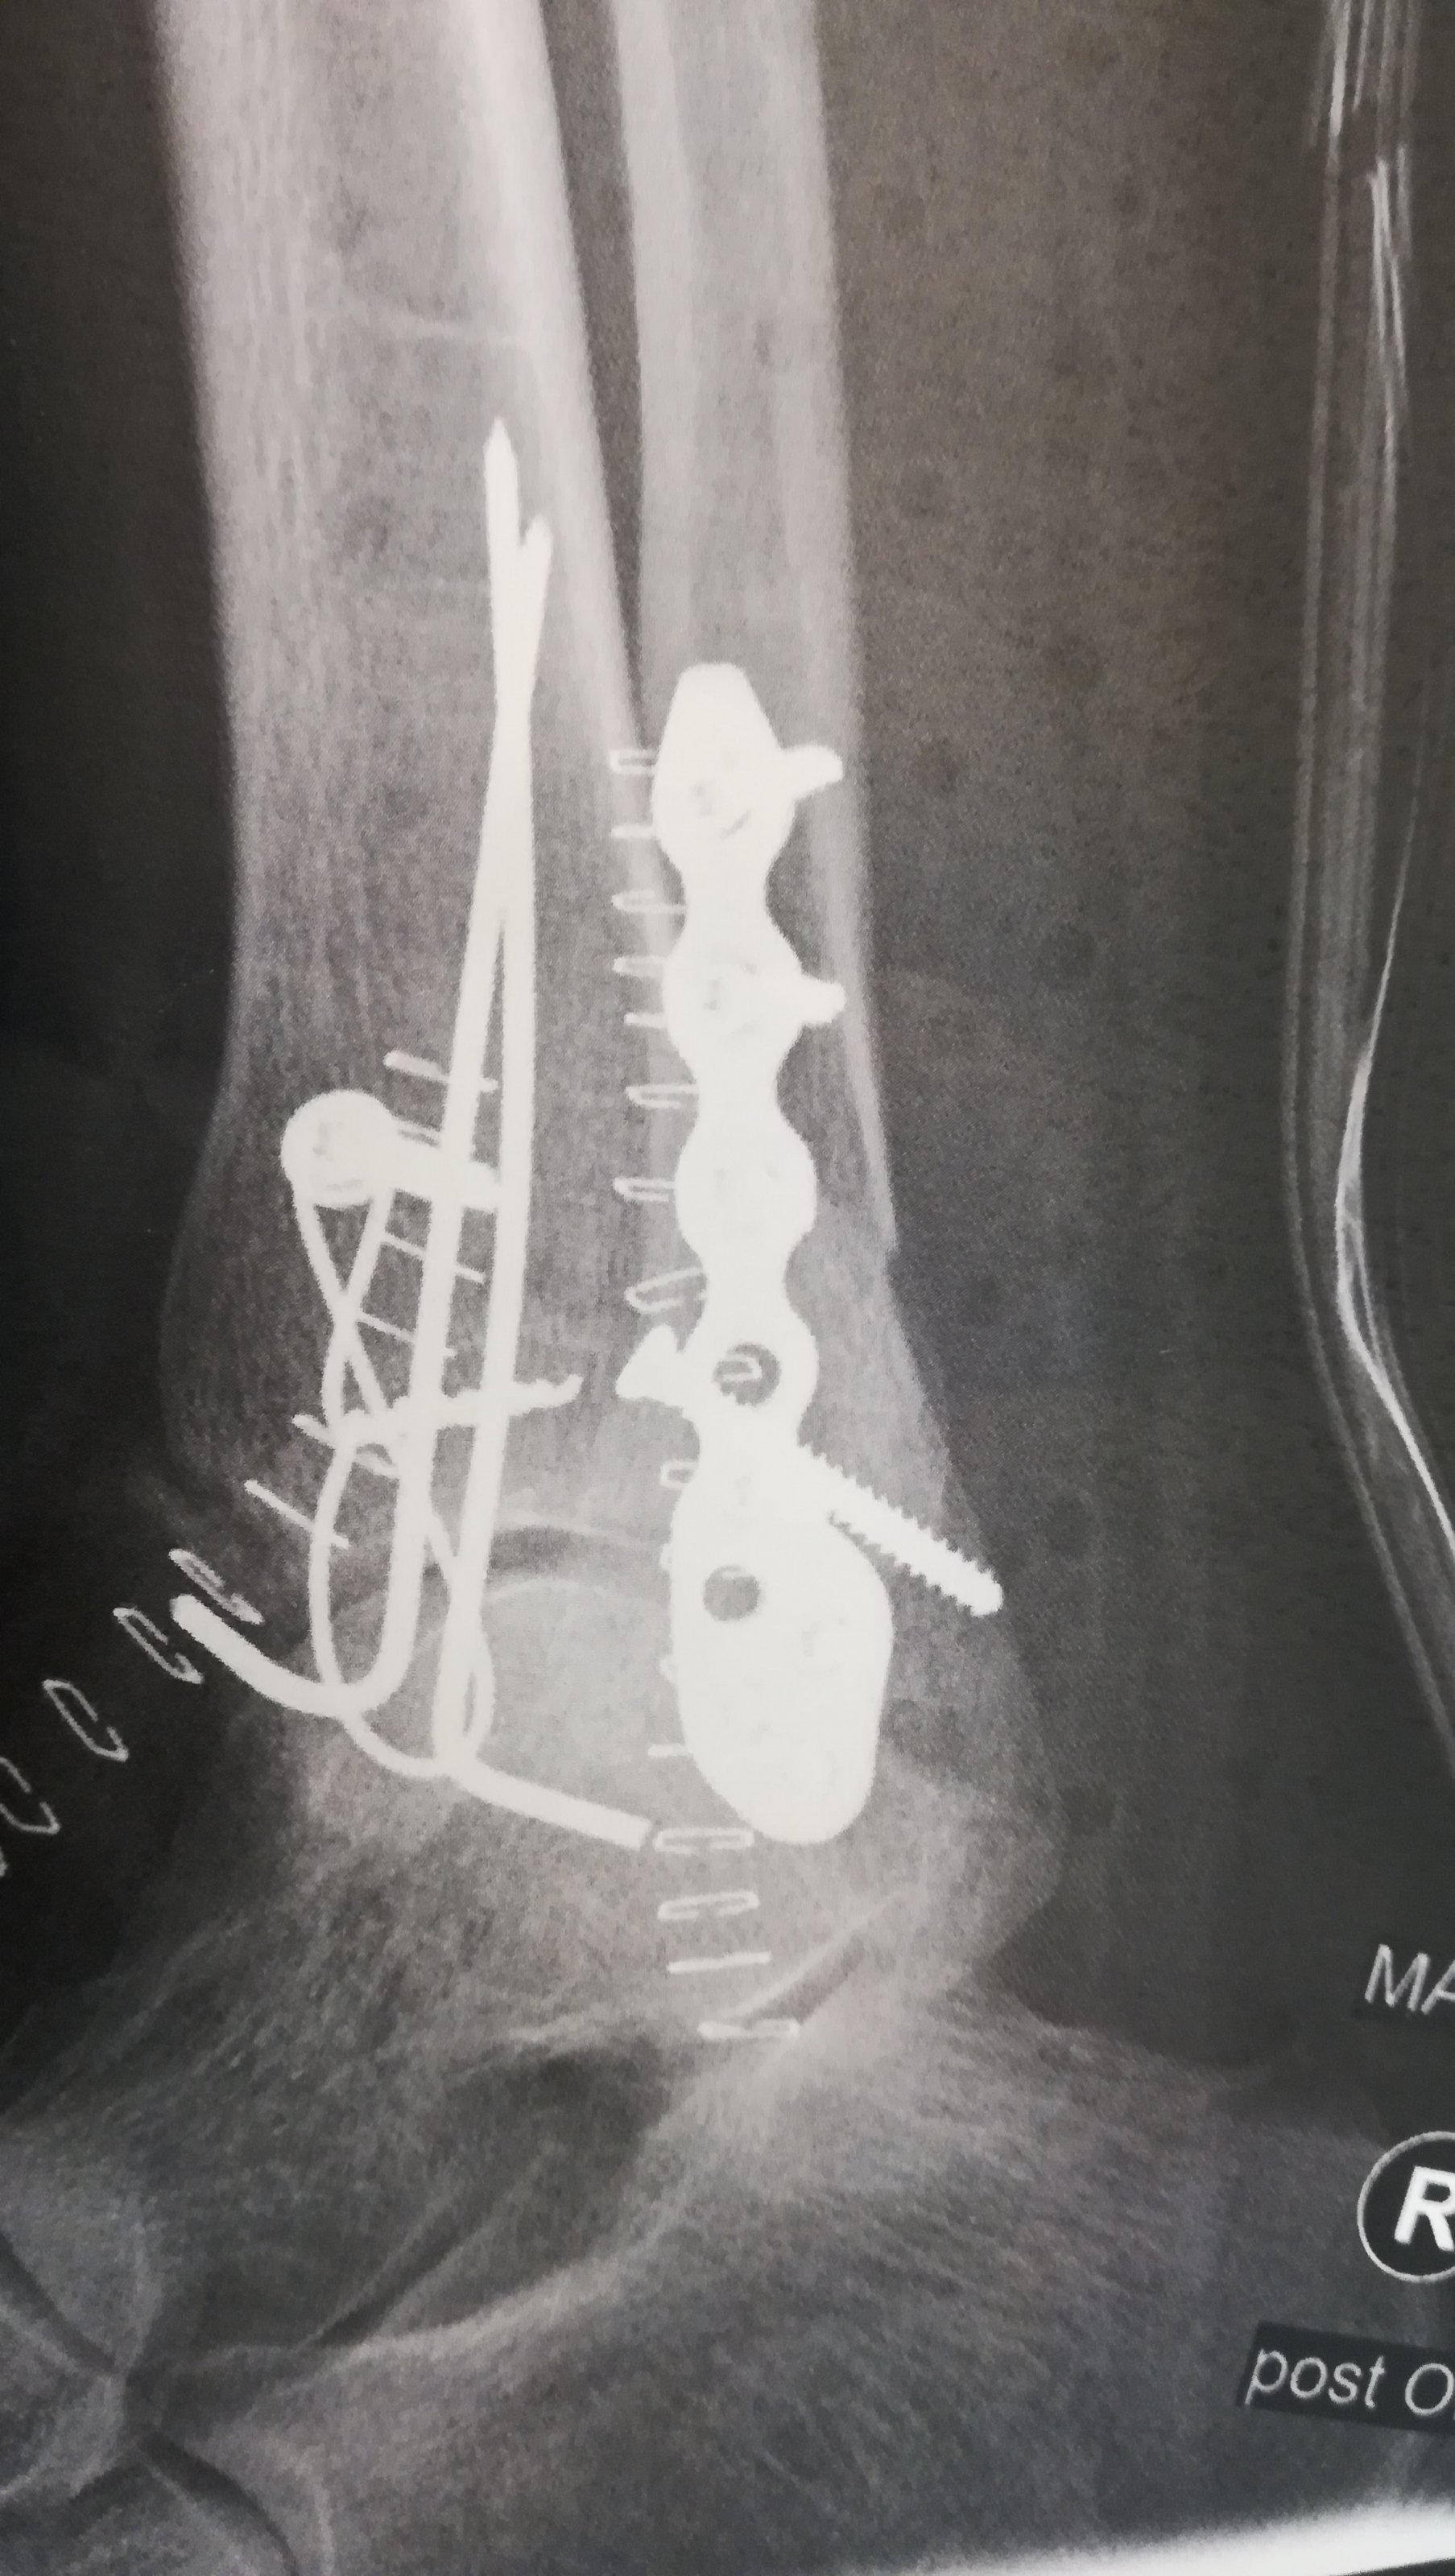

Sieht aus wie in ner Schraubenkiste ;-)...GUTE BESSERUNG!!Kurzes Update, Mein Fuß nach der Instandsetzung.Anhang anzeigen 430687Anhang anzeigen 430688

Danke, und das beste ist ich darf den ganzen Kram behalten.Sieht aus wie in ner Schraubenkiste ;-)...GUTE BESSERUNG!!

Schätze das Zeug wert, Titan ist teuerDanke, und das beste ist ich darf den ganzen Kram behalten.